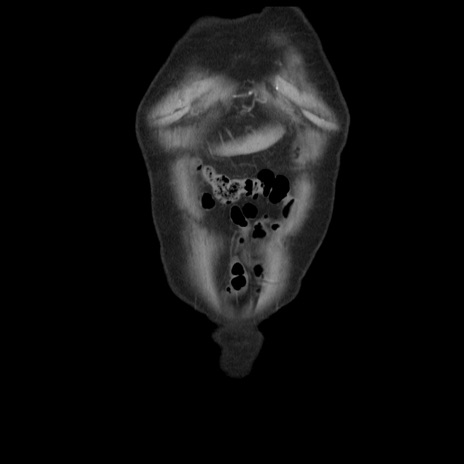

症例21(冠状断像)

【症例】70歳代男性

【主訴】腹痛

【現病歴】肝硬変・肝細胞癌にてかかりつけの方。約9時間前に食後より腹痛出現。症状が徐々に増悪し、嘔吐出現したため来院。

【既往歴】肝硬変、肝細胞癌(RFA、TACE後)

【身体所見】意識清明、表情苦悶様、BT 36℃、BP 129/78mmHg、P 88bpm、SpO2 97%(RA)、右上腹部から心窩部にかけて圧痛あり、反跳痛なし、筋性防御あり。

【データ】WBC 5800、CRP 0.16